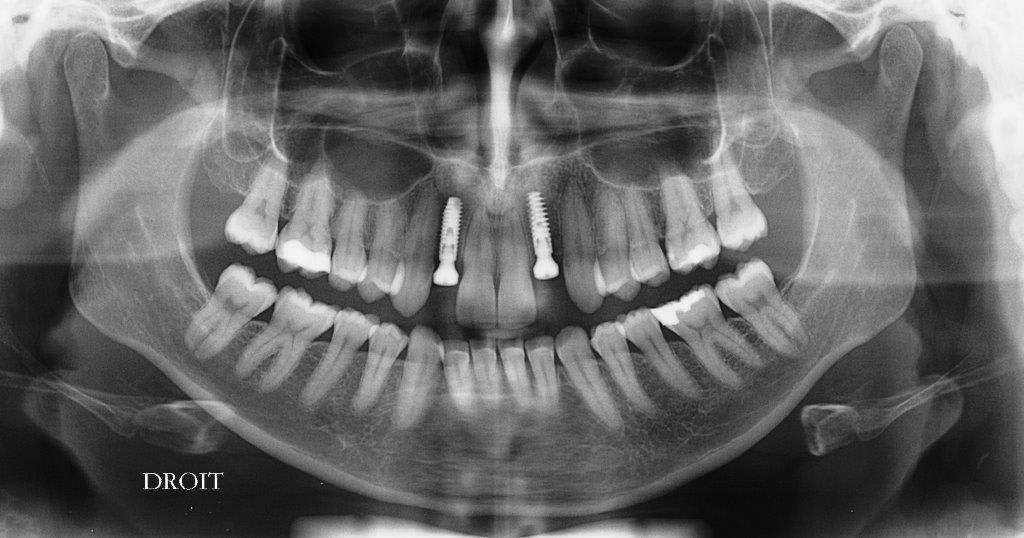

un autre petit cas courant, agénésie 12/22